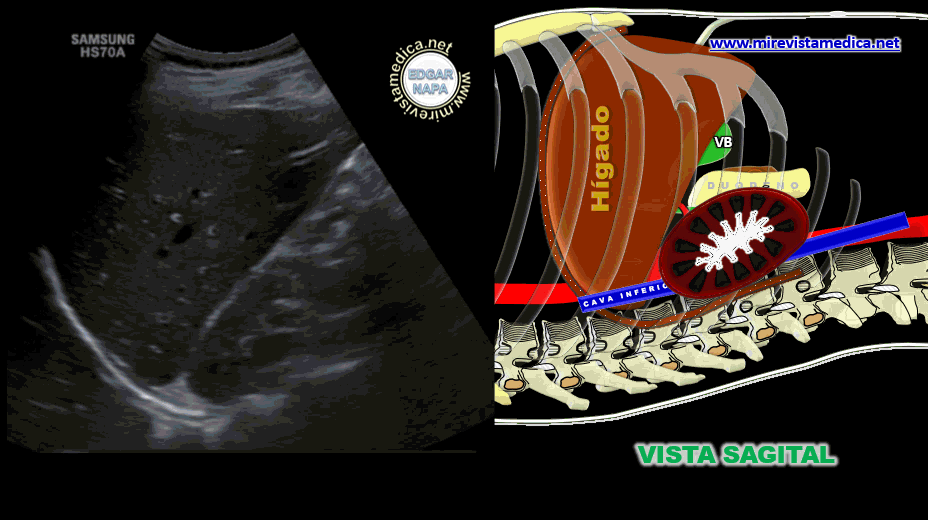

Esta cavidad peritoneal menor se comunica con la cavidad peritoneal mayor por medio del HIATO WINSLOW (3-4 cm.), Que está delimitado por:

• Adelante- pedículo Hepático.

• Atrás- Cava Inferior .

• Techo: lóbulo de Spiegel. (lóbulo caudado)

• Piso- 1° porción duodeno .